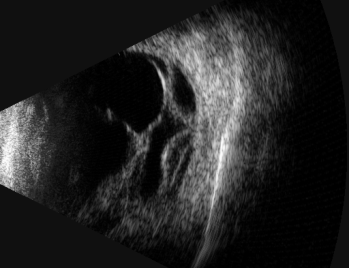

术前B超,显示外伤性视网膜脱离,眼内增殖严重